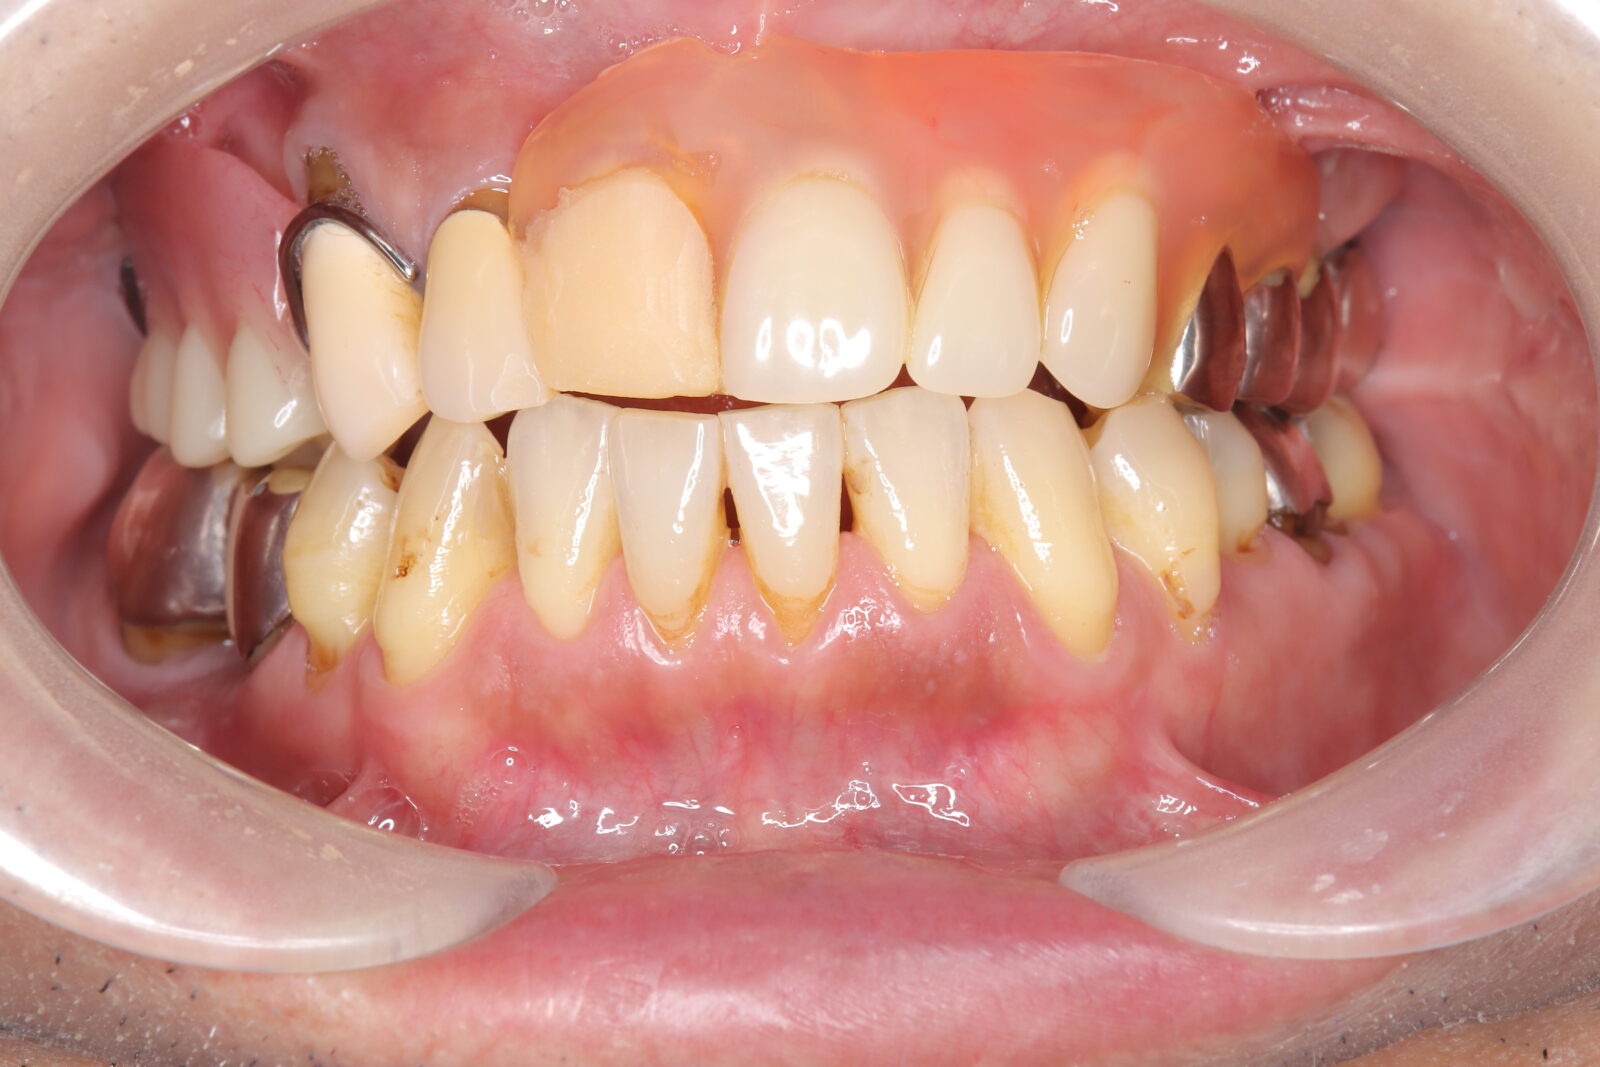

デンチャー+補綴+マウスピース矯正の症例

左上4〜7番に虫歯。右の親知らずの歯周ポケットは10mmあったため抜歯した。

左上6番の遠心は虫歯の範囲が大きすぎたため抜歯。義歯の安定を考慮すると、左上臼歯部をブリッジにするよりも、両側に義歯の人工歯を配置する方が良いと判断した。

本人の希望で薄く、口蓋を覆わない設計とした。

下顎前歯は抜歯後の治癒待ち、左上の虫歯治療中にインビザラインで歯列を整えた。

義歯作成期間中も歯の移動を行い、最終的には、計画通りに上顎の新義歯装着と同時に下顎のリテーナーを装着できた。

スマイルデンチャー

ジルコニアクラウン

インビザライン

治療期間約5ヶ月